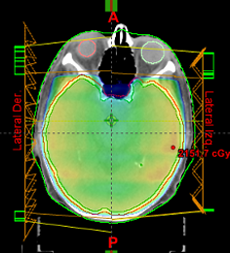

TRUEBEAM es la plataforma de tratamiento de Varian Medical Systems, líder mundial en la fabricación de aceleradores lineales. TRUEBEAM es un sistema poderoso y versátil que permite ejecutar desde tratamientos simples hasta los más complejos como IGRT y SBRT. Posee diversas energías de fotones y electrones para los tratamientos, lo que nos permite elegir la más conveniente para cada paciente. También emite haces de alta intensidad que incrementan hasta 6 veces la velocidad del depósito de energía, lo que permite administrar dosis altas en poco tiempo.

Tiene incorporado un sistema de tomografía por rayos X que permite durante la misma sesión de tratamiento, adquirir imágenes tomográficas del paciente para verificar su posición y ubicar el volumen en tratamiento.

También cuenta con un dispositivo que hace posible sincronizar la irradiación con la respiración del paciente. De tal manera que el haz de radiación solamente se encienda en un momento del ciclo del respiratorio, con lo cual, se reduce la irradiación de tejidos sanos aledaños.

En este sistema se pueden impartir tratamiento convencionales, 3D-conformacionales, IMRT, RapidArc y SBRT.

Eclipse v.15 es el sistema de planeación de tratamiento más moderno del que dispone Varian Medical Systems. Este le permite a los radioncólogos, dosimetristas y físicos médicos, a través de múltiples aplicaciones informáticas y algoritmos, realizar la planeación de los tratamientos de radioterapia en un entorno totalmente digital y tridimensional para visualizar la dosis que recibirán los volúmenes de tratamiento y, al mismo tiempo, encontrar la configuración óptima minimizando la dosis en los tejidos sanos.